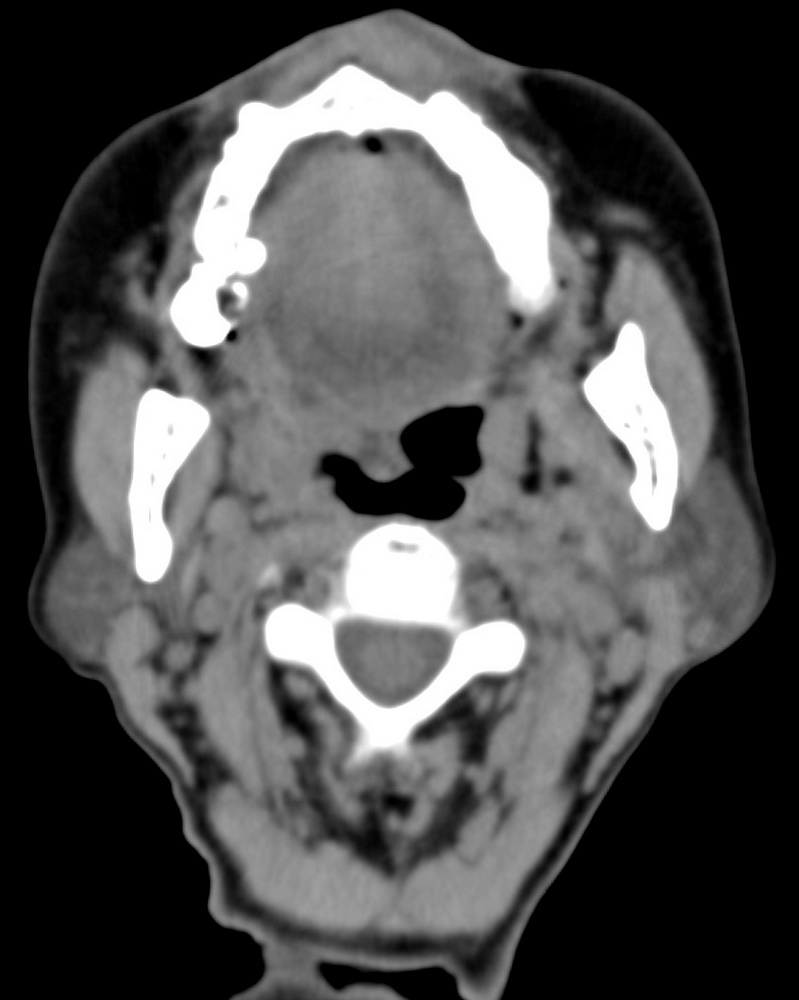

女,68岁。发现上唇无痛性肿块2年多,查体局部皮肤隆起,其余未见异常。

病灶ct值约42hu。

病理结果:唾液腺混合瘤。

感谢楼主反馈结果!结合结果考虑应该是小唾液腺。

上唇唾液腺混合瘤,罕见!学习了!